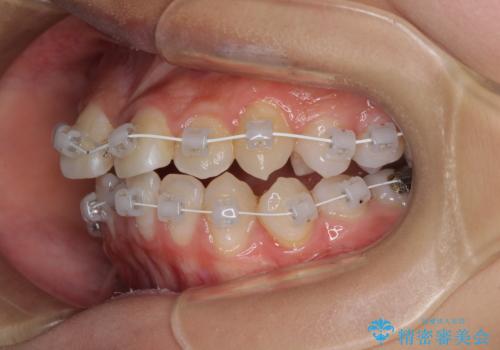

急速拡大装置を用いて上顎骨を側方に拡大し、上顎の叢生を解消するとともに下顎歯列拡大により下顎の叢生も解消することとしました。

急速拡大装置使用直後は著しいスペースが正中に発現するため、ワイヤー矯正を行いますが、今回は治療期間を短くしたいとのことで、上下全体をワイヤー装置にて矯正治療することとしました。